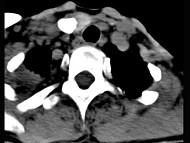

问题 50岁女性患者,体检发现右侧甲状腺有较硬结节,CT扫描如图所示,请选择正确的描述和答案()

选项 A.右侧甲状腺内见稍低密度影,周边围以环形致密钙化影 B.肿块影与周围结构分界清楚 C.考虑为结节性甲状腺肿 D.考虑为甲状腺癌 E.考虑为甲状腺腺瘤钙化

答案 ABE